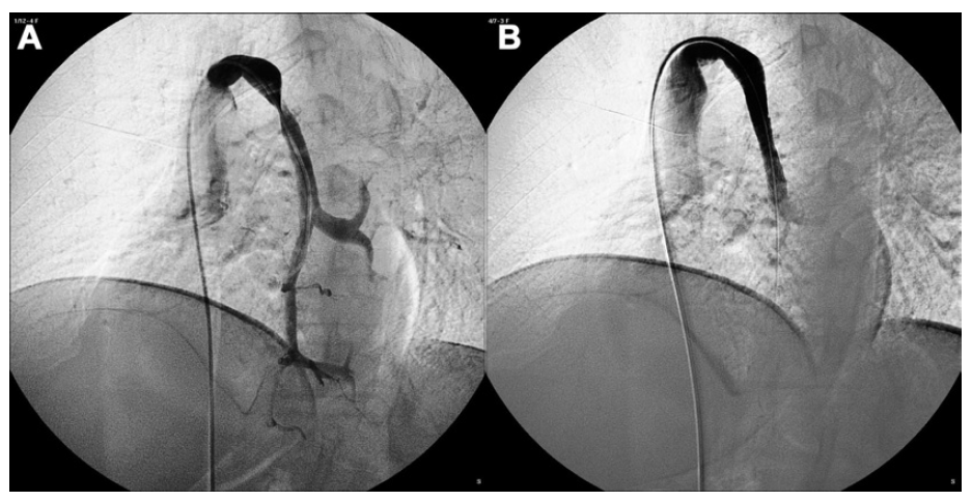

La foto a fianco rappresenta il catetere e il “pallone” usati nella PTA (angioplastica percutanea transluminale)